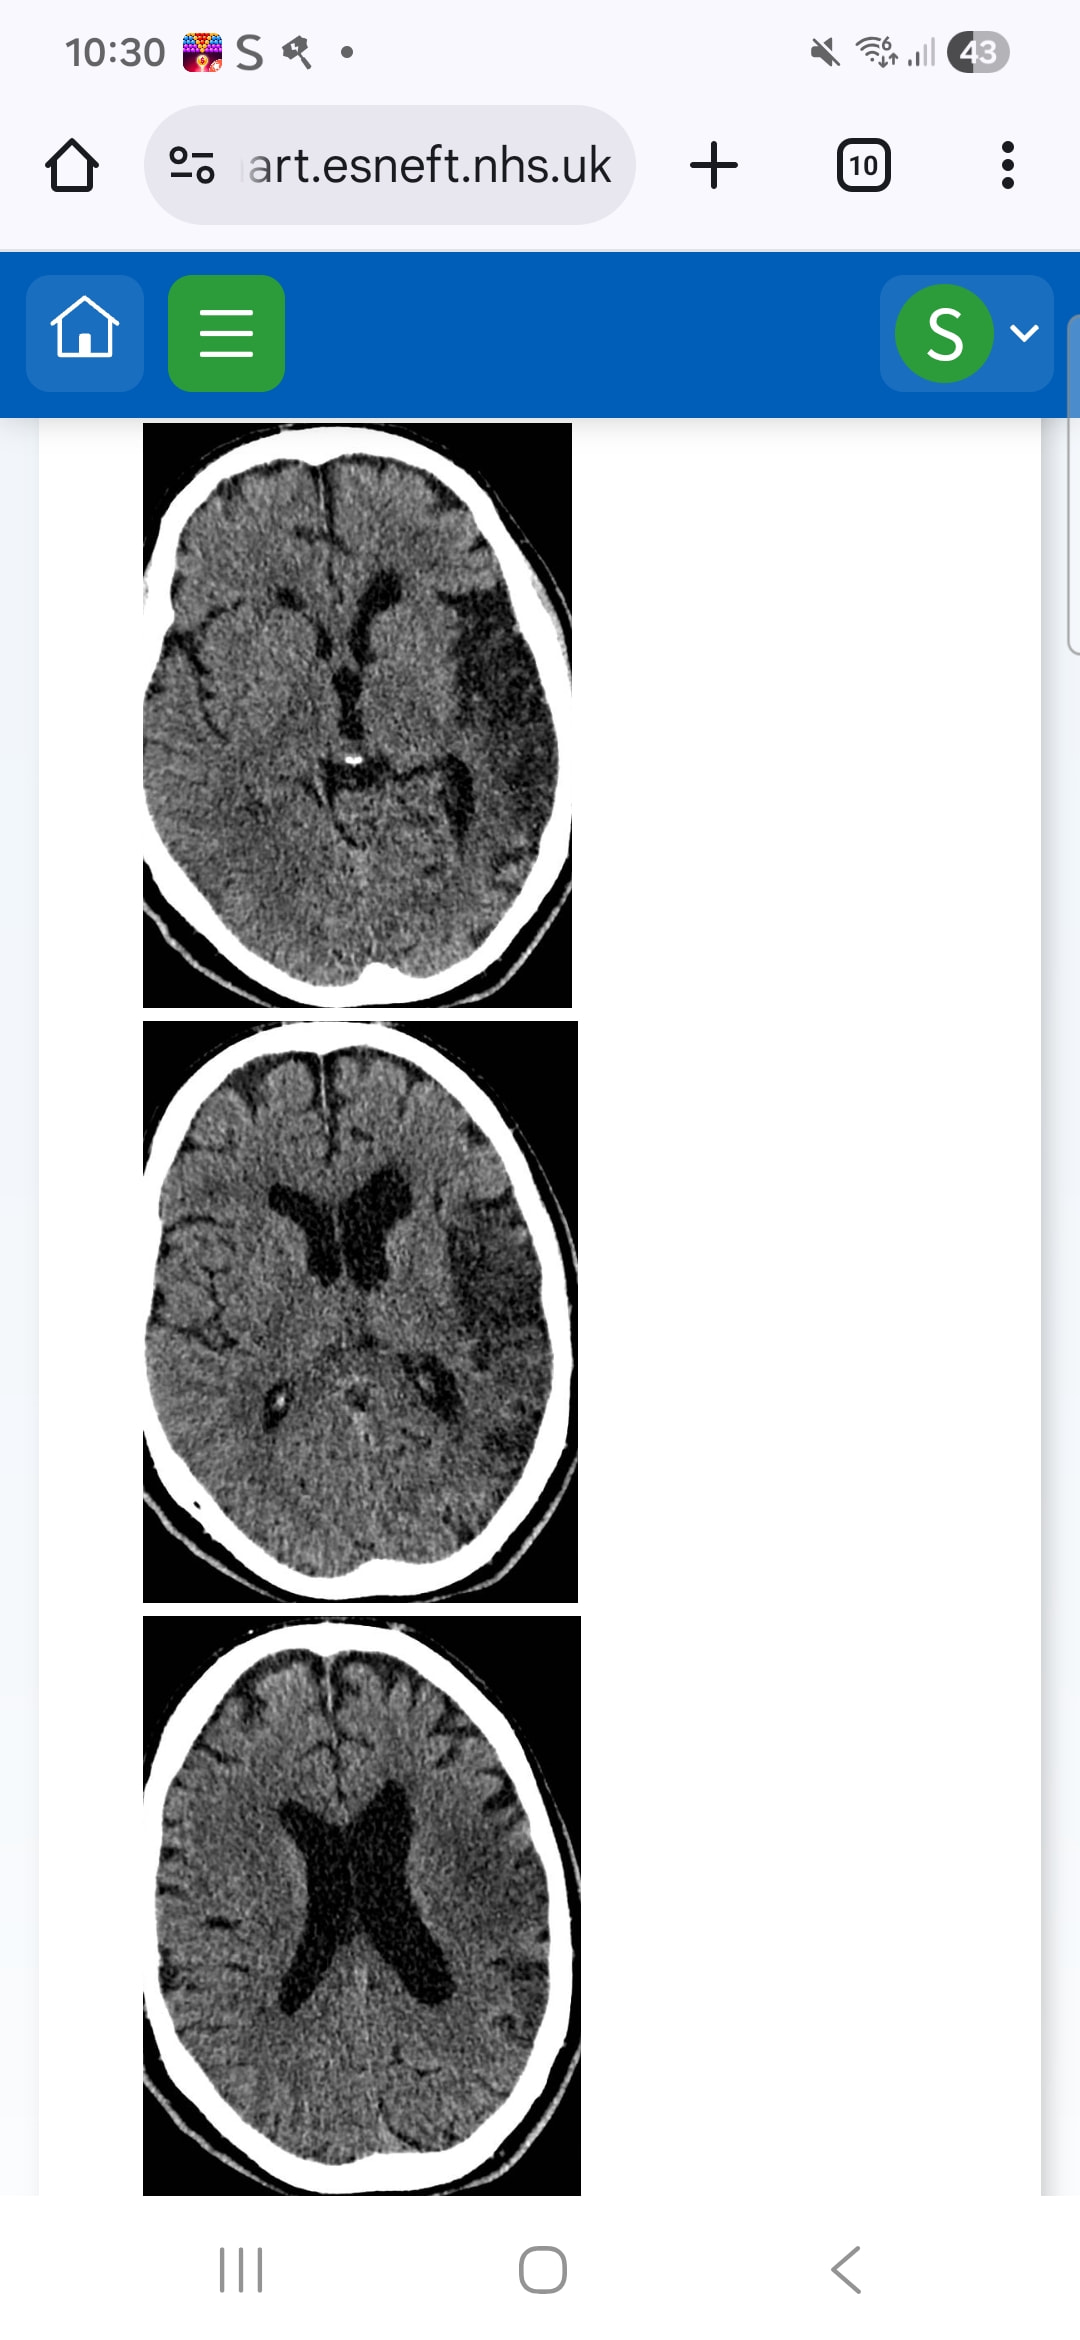

Having analysed the graphics, I would say the stroke is not that bad at all.

But from a recovery point of view, this graphic alone does not tell the full story and I believe we need to look at other factors such as age of patient, health condition prior to stroke, lifestyle prior to stroke, job etc.

I would say still say this is not a bad stroke at all.

I see no reason why there should not be a very good recovery and return to as normal as you can get from having had a stroke.

So his was the right and didn’t effect his left arm or leg or vision, am I right in thinking? Just his speech?

It looks like a large bleed. Did he have a bleed? If on the left it is a bleed, it covers quite a significant portion of the brain. I am not a neurologist, obviously, more a brain sparky. I am to understand that where symptoms are concerned, it is more about location than size.

He didnt have a bleed. It was a blood clot

Ah, then I have failed my first efforts into radiology. I can’t see the damage in the scans. However, that doesn’t mean the outcome of the stroke isn’t significant for your partner.

Hi @Clairekirby1990 if I’m reading it right as doing this from memory looks very similar to mine - a right sided ischemic stroke, I was lucky and physically rehabbed very well as such. My arm took work then my hand but was lucky to have no damage to vision etc but it still was a bit of a shock. Let your partner take his time and recover properly, he may well get back to work like I did but patience, support and some understanding from his employer will be key. Get support for all of you because it’s needed and it’s out there and don’t be afraid to ask others for help. There are some truly magnificent minds on the subject here with so much practical experiences that can guide you if needed.